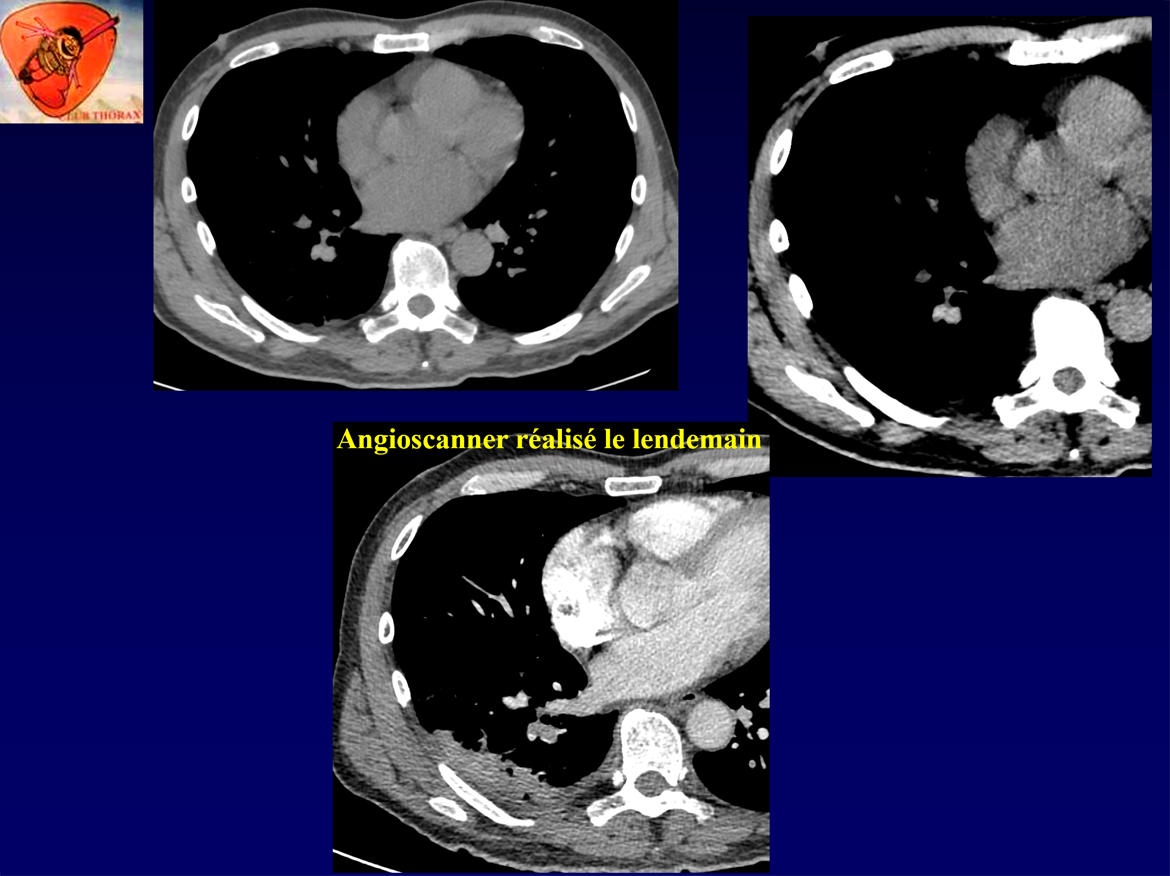

Homme, 59 ans.

Douleur lombaire droite hyperalgique.

Hyperleucocytose.

Suspicion de colique néphrétique ou de pyélonéphrite droite.

Scanner AP en urgence, qui innocente les reins, mais sur la base thoracique…